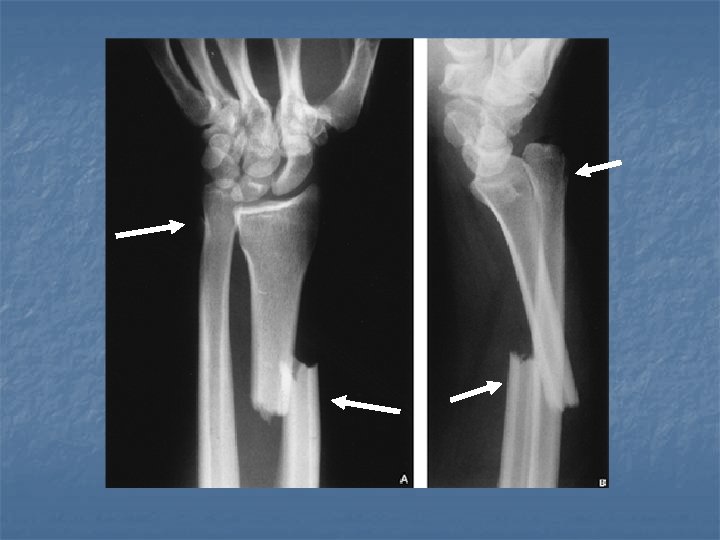

Colles Fracture n n n Most frequently encountered injury to the distal forearm. Fall on the outstretched hand with forearm pronated in dorsiflexion. Age usually above 50 y; F>M. Extraarticular 2 -3 cm away from articular surface of radius. Associated # of ulnar styloid process